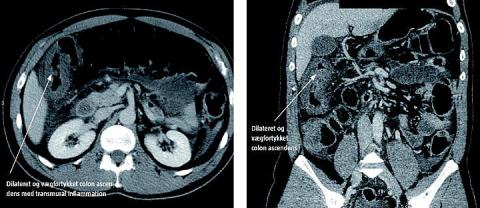

En 48-årig mand blev indlagt med en verotoksinproducerende Escherichia coli (VTEC)-gastroenteritis, som han havde erhvervet i Tyskland. Patienten blev indlagt på grund af tiltagende mavekrampelignende smerter og blodige afføringer. Han fik foretaget akut computertomografi af abdomen. Skanningen viste patologisk vægfortykkelse af colon ascendens og transversum med transmural inflammation samt caecum dilateret til 8 cm. På billederne ses en vægfortykket og dilateret colon ascendens med transmural inflammation. Man valgte at observere patienten natten over, men da smerterne tiltog i det første døgn under indlæggelsen, foretog man en oversigt over abdomen, der viste en tiltaget caecum dilatation på op til 15 cm. Abdominalkirurgerne foretog akut højresidig hemikolektomi, da caecum var perforationstruet. Patologisvaret viste forandringer, der svarede til en pseudomembranøs enterokolitis. Operationen og det postoperative forløb, hvor patienten fik meropenemtrihydrat 1 g × 3 dagligt i fem dage, var ukompliceret.